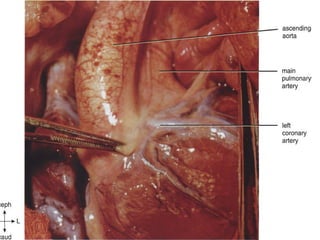

 Usually arise from the aortic sinuses that face the

pulmonary trunk, regardless of the inter-

relationships of the great arteries.

 Thus, the noncoronary sinus is usually the anterior

one.